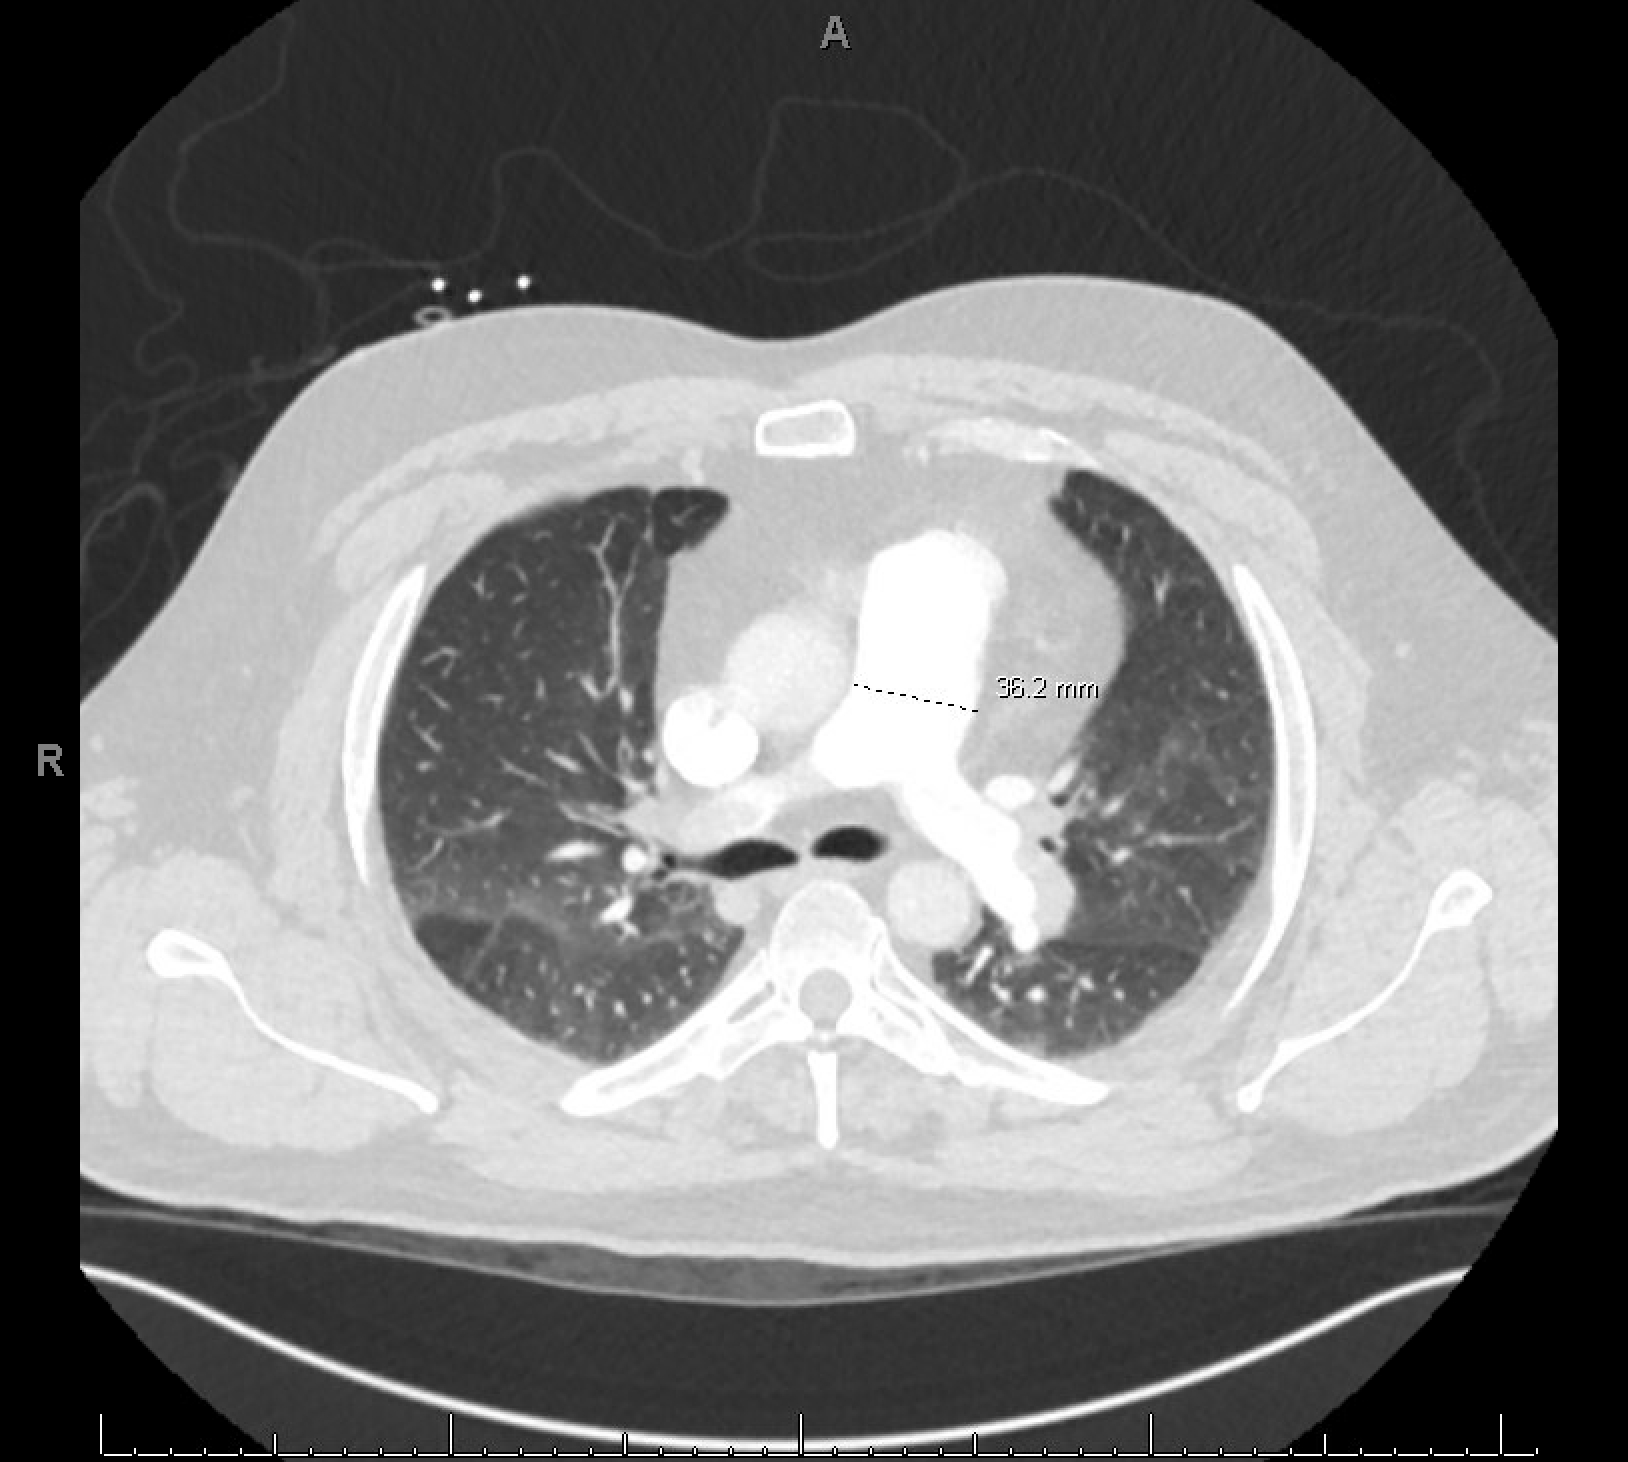

A 44-year-old male with a remote history of resected melanoma presented with acute-onset left upper extremity numbness and discoloration, progressing proximally. He also reported worsening dyspnea over one week. Physical exam revealed an absent left radial pulse and oxygen requirement of 6L via nasal cannula. CT angiography identified a left axillary artery thrombus with distal brachial artery reconstitution and bilateral pulmonary emboli. RV strain was confirmed by an RV/LV ratio of 1.2. Transthoracic echocardiogram demonstrated RV dilation and dysfunction, with a suspected PFO.